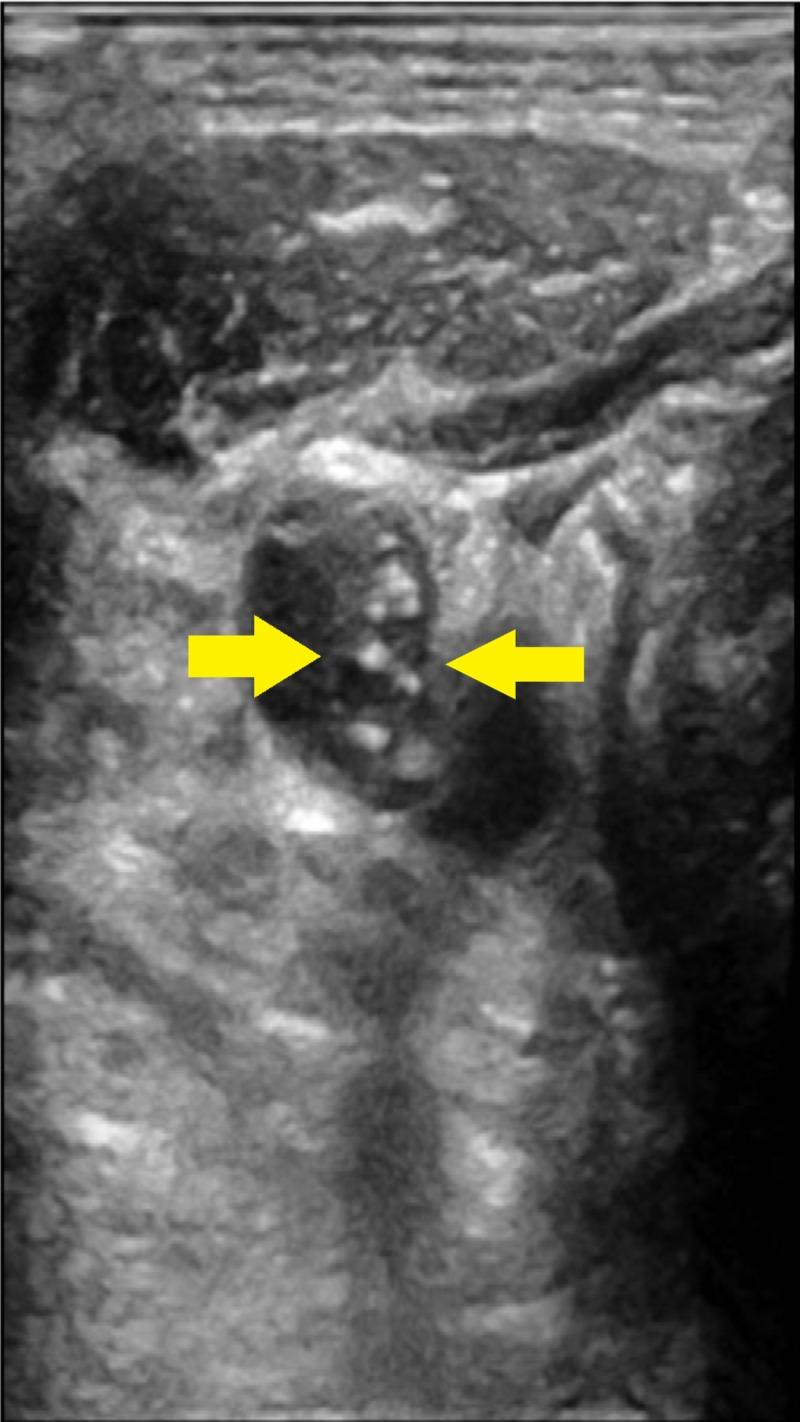

Lemierre syndrome is a life-threatening condition associated with infection by obligate anaerobes residing in oropharyngeal mucosa. The most common organism responsible is Fusobacterium necrophorum. We report a case in a 69-year-old gentleman. The man with past medical history of hypertension, anxiety and chronic alcohol abuse was brought in by his family for altered mental status and fever. He had a complicated stay with septic shock on multiple pressors, his blood cultures grew Fusobacterium necrophorum and neck ultrasound showed acute thrombus of the right internal jugular vein (IJV). The patient had received intravenous antibiotics throughout stay but had poor prognosis and eventually expired after a complicated hospital stay. Lemierre syndrome is a rare syndrome usually associated with an acute oropharyngeal infection due to anaerobic bacteria leading to secondary septic thrombophlebitis of the internal jugular vein. The characteristic clinical picture noticed is a hematogenous progression to distant septic emboli. It is a life-threatening condition and a prompt diagnosis is critical for preventing fatal consequences. The purpose of this case report is to increase awareness about this clinical condition among medical professionals.

勒米尔综合征是一种危及生命的疾病,与口咽黏膜中存在的专性厌氧菌感染有关。最常见的致病微生物是坏死梭杆菌。我们报告一例69岁男性病例。该男子有高血压、焦虑症和慢性酒精滥用病史,因精神状态改变和发热被家人送来就医。他住院过程复杂,出现感染性休克,需多种升压药维持,血培养检出坏死梭杆菌,颈部超声显示右侧颈内静脉急性血栓形成。患者住院期间一直接受静脉抗生素治疗,但预后不佳,在经历复杂的住院过程后最终死亡。勒米尔综合征是一种罕见综合征,通常与厌氧菌引起的急性口咽感染有关,导致颈内静脉继发性感染性血栓性静脉炎。其特征性临床表现是血行播散至远处的感染性栓子。这是一种危及生命的疾病,及时诊断对于预防致命后果至关重要。本病例报告的目的是提高医学专业人员对这种临床疾病的认识。